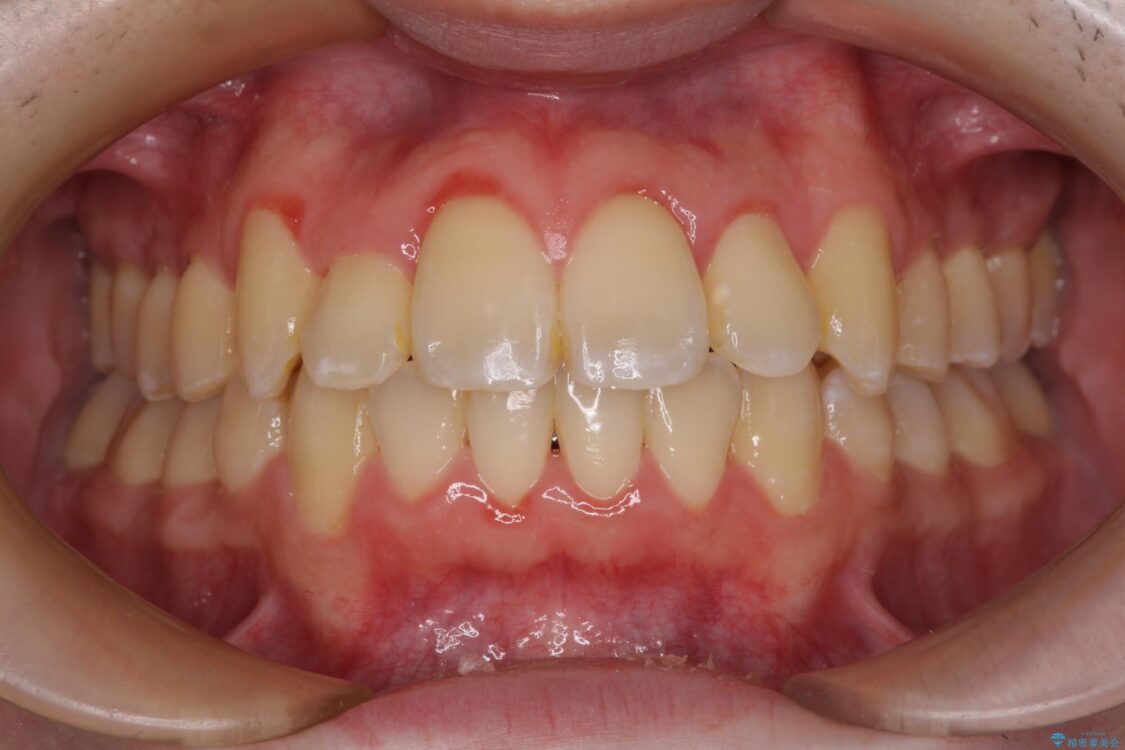

八重歯や奥歯の噛みにくさを気にして来院された患者様です。

前歯のクロスバイトや八重歯の他に、左右最後臼歯のシザーズバイト(鋏状咬合)が認められました。

シザーズバイト改善のために補助装置を使用しながら、ワイヤー装置にて全体の歯列を整えることとしました。

治療前